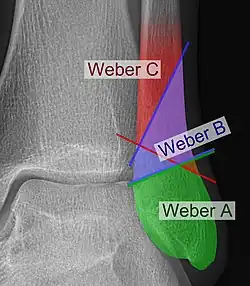

Danis–Weber classification on X-ray.

The Danis–Weber classification (often known just as the Weber classification) is a method of describing ankle fractures. It has three categories:[1]

Type A

Fracture of the fibula distal to the syndesmosis (the connection between the distal ends of the tibia and fibula). Typical features:

• below level of the ankle joint

• tibiofibular syndesmosis intact

• deltoid ligament intact

• medial malleolus occasionally fractured

• usually stable: occasionally nonetheless requires an open reduction and internal fixation (ORIF) particularly if medial malleolus fractured

Type B

Fracture of the fibula at the level of the syndesmosis. Typical features:

• at the level of the ankle joint, extending superiorly and laterally up the fibula

• tibiofibular syndesmosis intact or only partially torn, but no widening of the distal tibiofibular articulation

• medial malleolus may be fractured or deltoid ligament may be torn

• variable stability

Type C

Fracture of the fibula proximal to the syndesmosis. Typical features:

• above the level of the ankle joint

• tibiofibular syndesmosis disrupted with widening of the distal tibiofibular articulation

• medial malleolus fracture or deltoid ligament injury present

• unstable: requires ORIF

Categories B and C imply a degree of damage to the syndesmosis itself (which cannot be directly visualised on X-ray). They are inherently unstable and are more likely to require operative repair to achieve a good outcome. Type A fractures are usually stable and can be managed with simple measures, such as a plaster of paris cast.